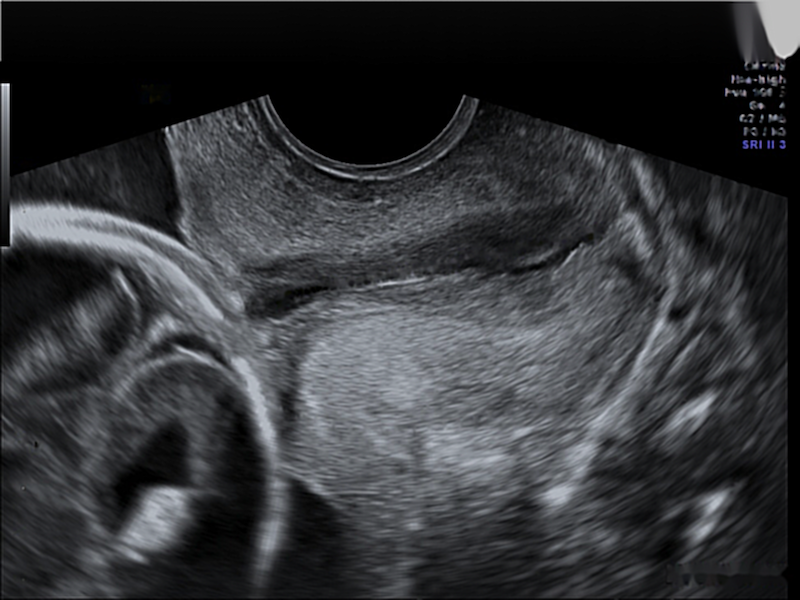

Dataset: The original dataset consists of 354 two-dimensional transvaginal cervical ultrasound images. Data were collected from female volunteers during check-ups conducted in the first and second trimesters of pregnancy. Data includes 319 images of the pregnancy control group and 35 images of premature deliveries which reflects the statistical occurrence of this phenomenon in reality. Note that to get information about image labels, we waited for the pregnancy result of each patient. The data was provided by two different clinics: King’s College London and Medical University of Warsaw. All images have been annotated by several independent gynecologist experts via our own annotation tool. Sample images from the data set are depicted in Fig. 1.

The annotations received contained the study identifier and four control points which allowed for the drawing of cubic Bézier curves that outlined the shape and position of the cervix in the image. Bézier curves were used to create masks for cervical segmentation.